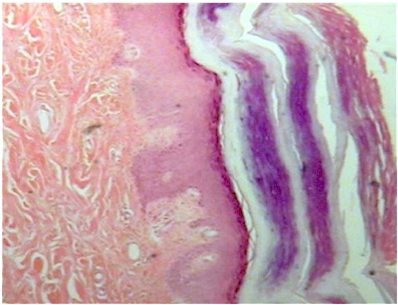

Thick Keratinized skin